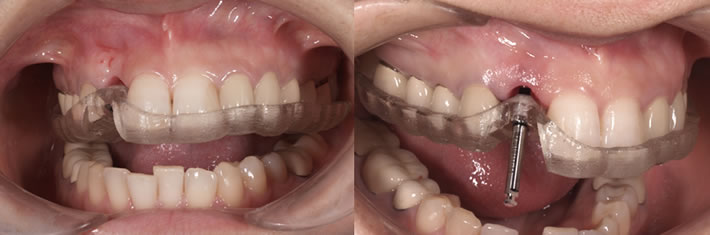

前歯のインプラント症例では、コンピュータシミュレーションに基づいたサージカルテンプレートを使用します。

精密な、診査・診断・プランニングを通じて、審美的(見た目)・機能的(咬み合わせ)に、どこにインプラントを埋入するのが正解なのかをシミュレーションした上で、ガイデッドサージェリーという手法で寸分違わぬ位置にインプラントを埋入します。 無計画に骨のある位置に埋入するのではなく、正しい位置にインプラントを埋入するために必要に応じて骨造成(骨を増やす処置)を行います。